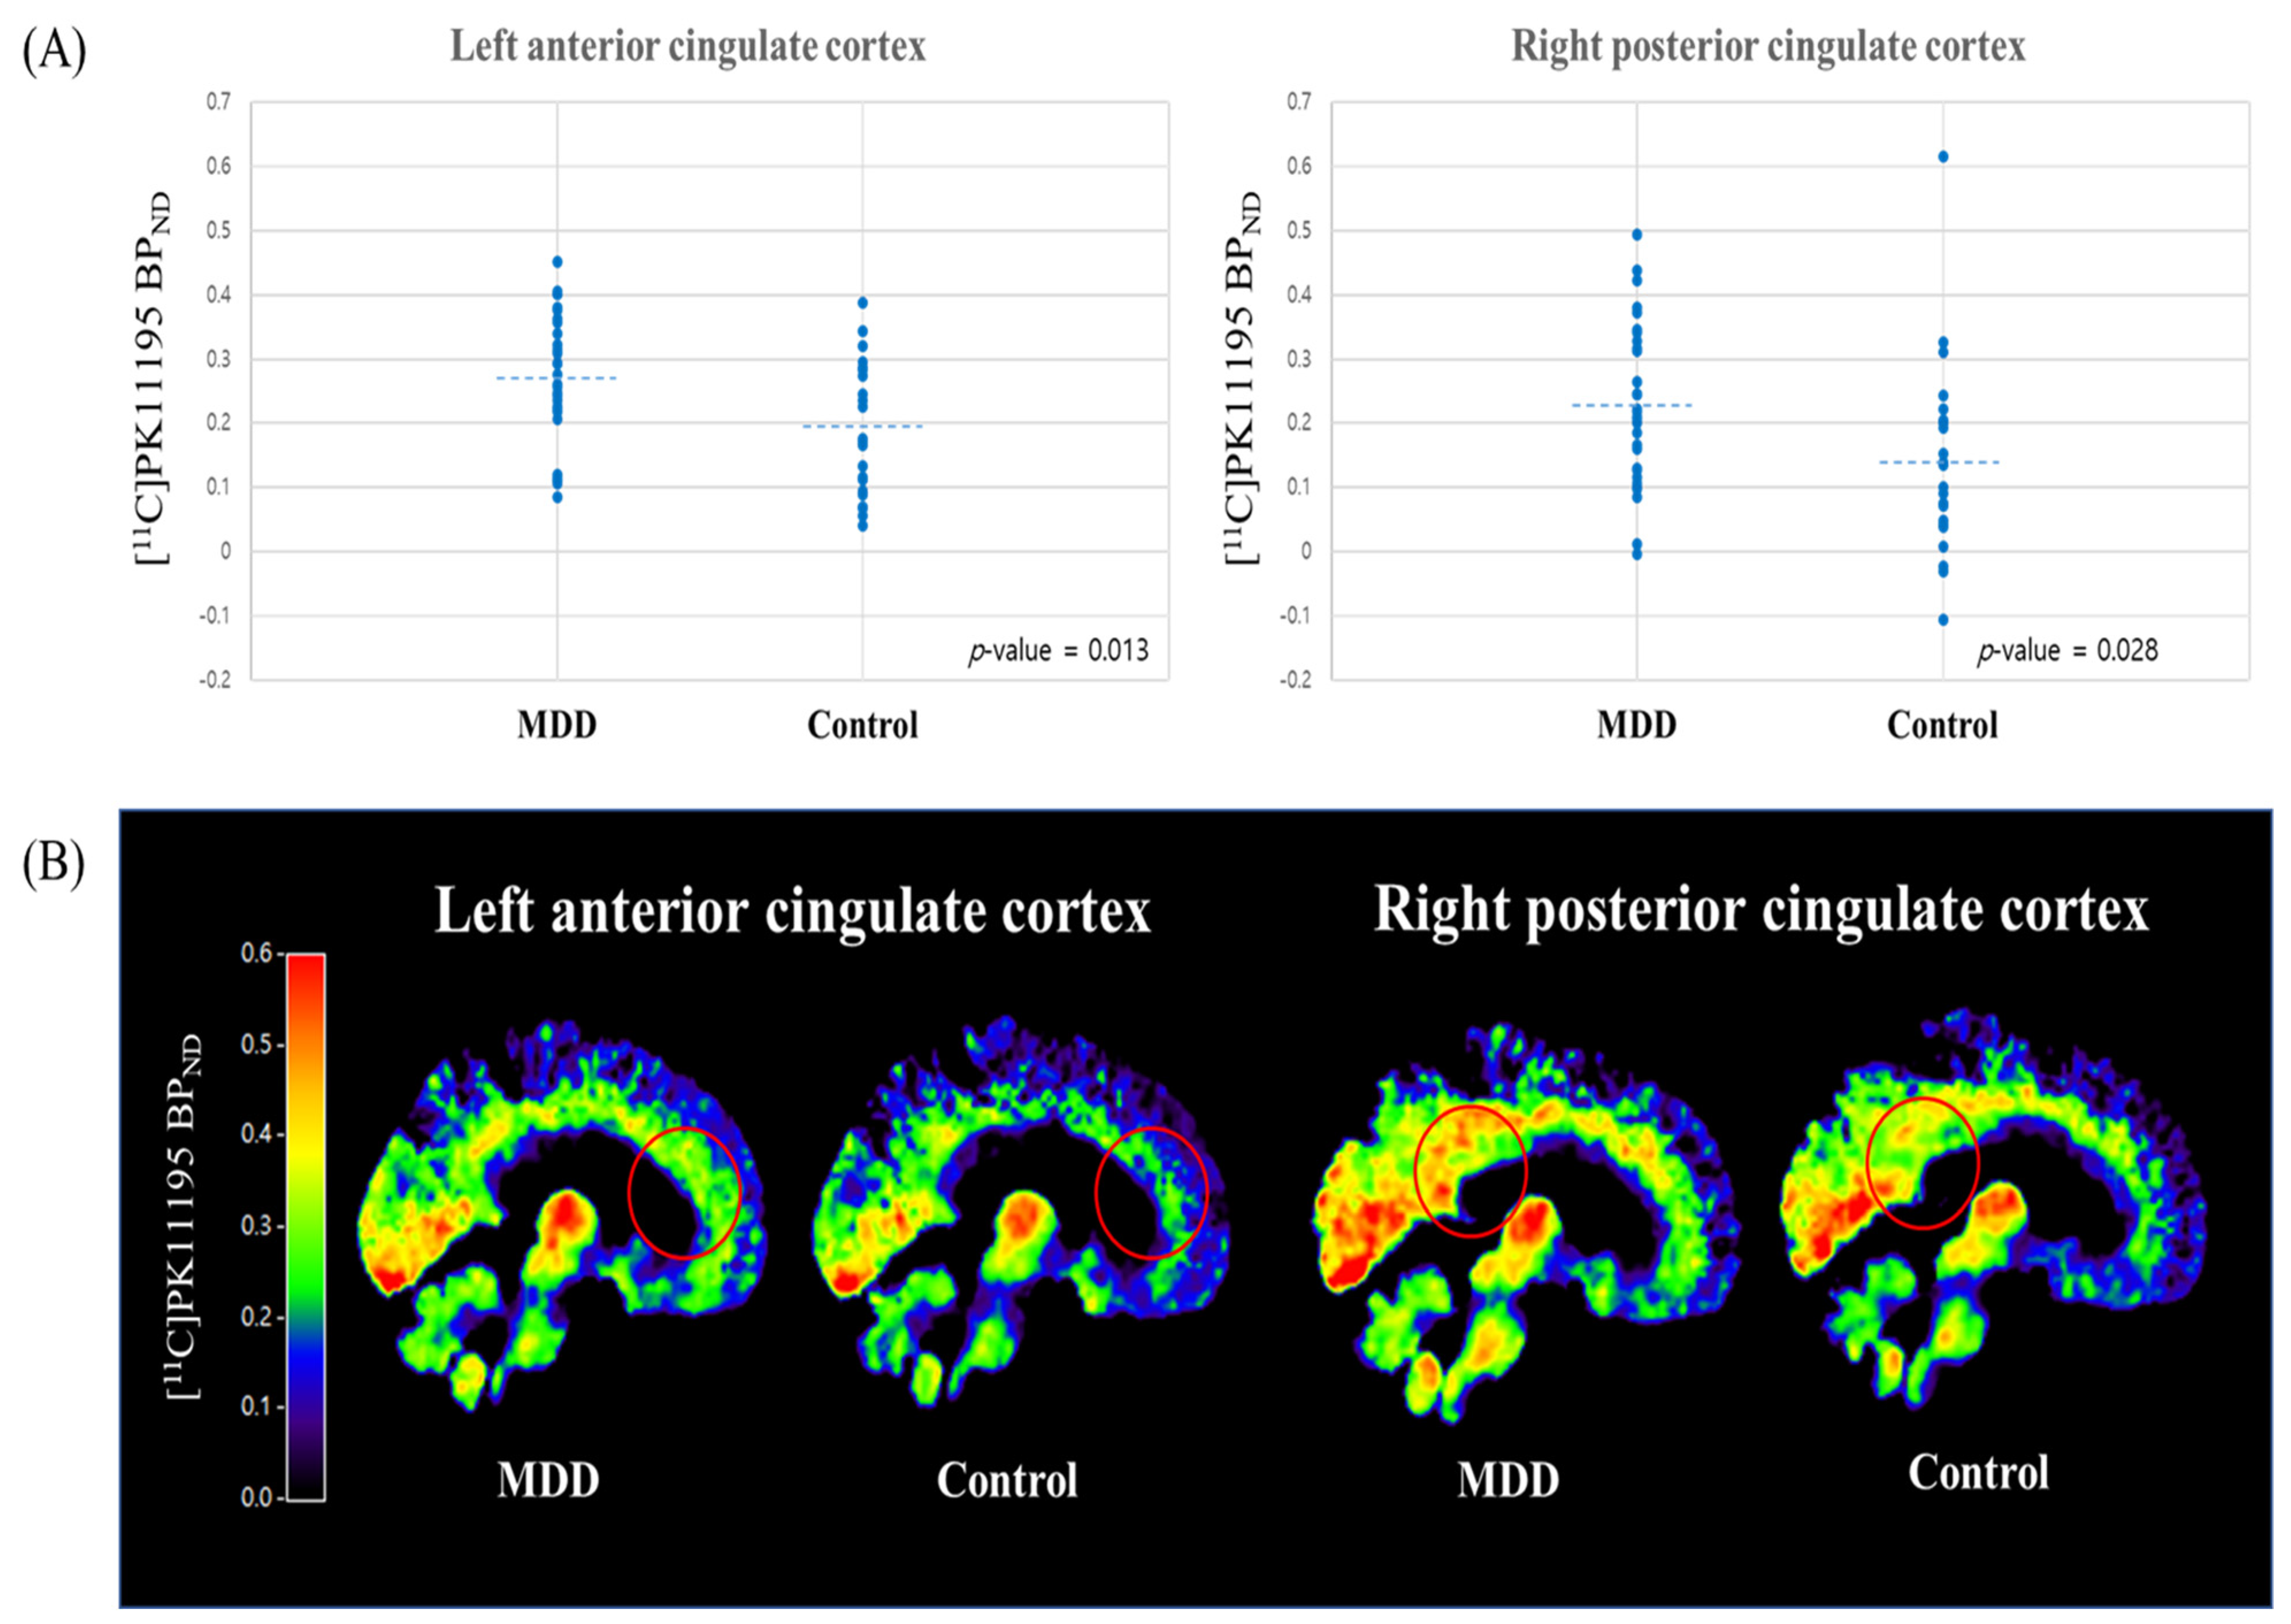

| ROIs | [11C]PK11195 BPND Value | t-Value | p-Value | Effect Size (Cohen’s d) | |

|---|---|---|---|---|---|

| MDD Group Mean (SD) | Control Group Mean (SD) | ||||

| Lt. PFC | 0.245 (0.103) | 0.194 (0.104) | 1.783 | 0.080 † | 0.494 |

| Rt. PFC | 0.234 (0.099) | 0.192 (0.105) | 1.491 | 0.142 | 0.413 |

| Lt. ACC | 0.268 (0.103) | 0.195 (0.104) | 2.572 | 0.013 * | 0.713 |

| Rt. ACC | 0.157 (0.090) | 0.115 (0.103) | 1.577 | 0.121 | 0.437 |

| Lt. PCC | 0.251 (0.122) | 0.200 (0.130) | 1.467 | 0.149 | 0.407 |

| Rt. PCC | 0.228 (0.126) | 0.142 (0.150) | 2.269 | 0.028 * | 0.629 |

| Lt. insula | 0.272 (0.114) | 0.232 (0.122) | 1.240 | 0.221 | 0.344 |

| Rt. insula | 0.338 (0.125) | 0.294 (0.137) | 1.221 | 0.228 | 0.338 |

| Lt. hippocampus | 0.165 (0.088) | 0.134 (0.092) | 1.222 | 0.227 | 0.339 |

| Rt. hippocampus | 0.129 (0.086) | 0.099 (0.078) | 1.347 | 0.184 | 0.373 |

| Lt. temporal cortex | 0.159 (0.097) | 0.124 (0.088) | 1.388 | 0.171 | 0.385 |

| Rt. temporal cortex | 0.170 (0.090) | 0.133 (0.082) | 1.540 | 0.130 | 0.427 |